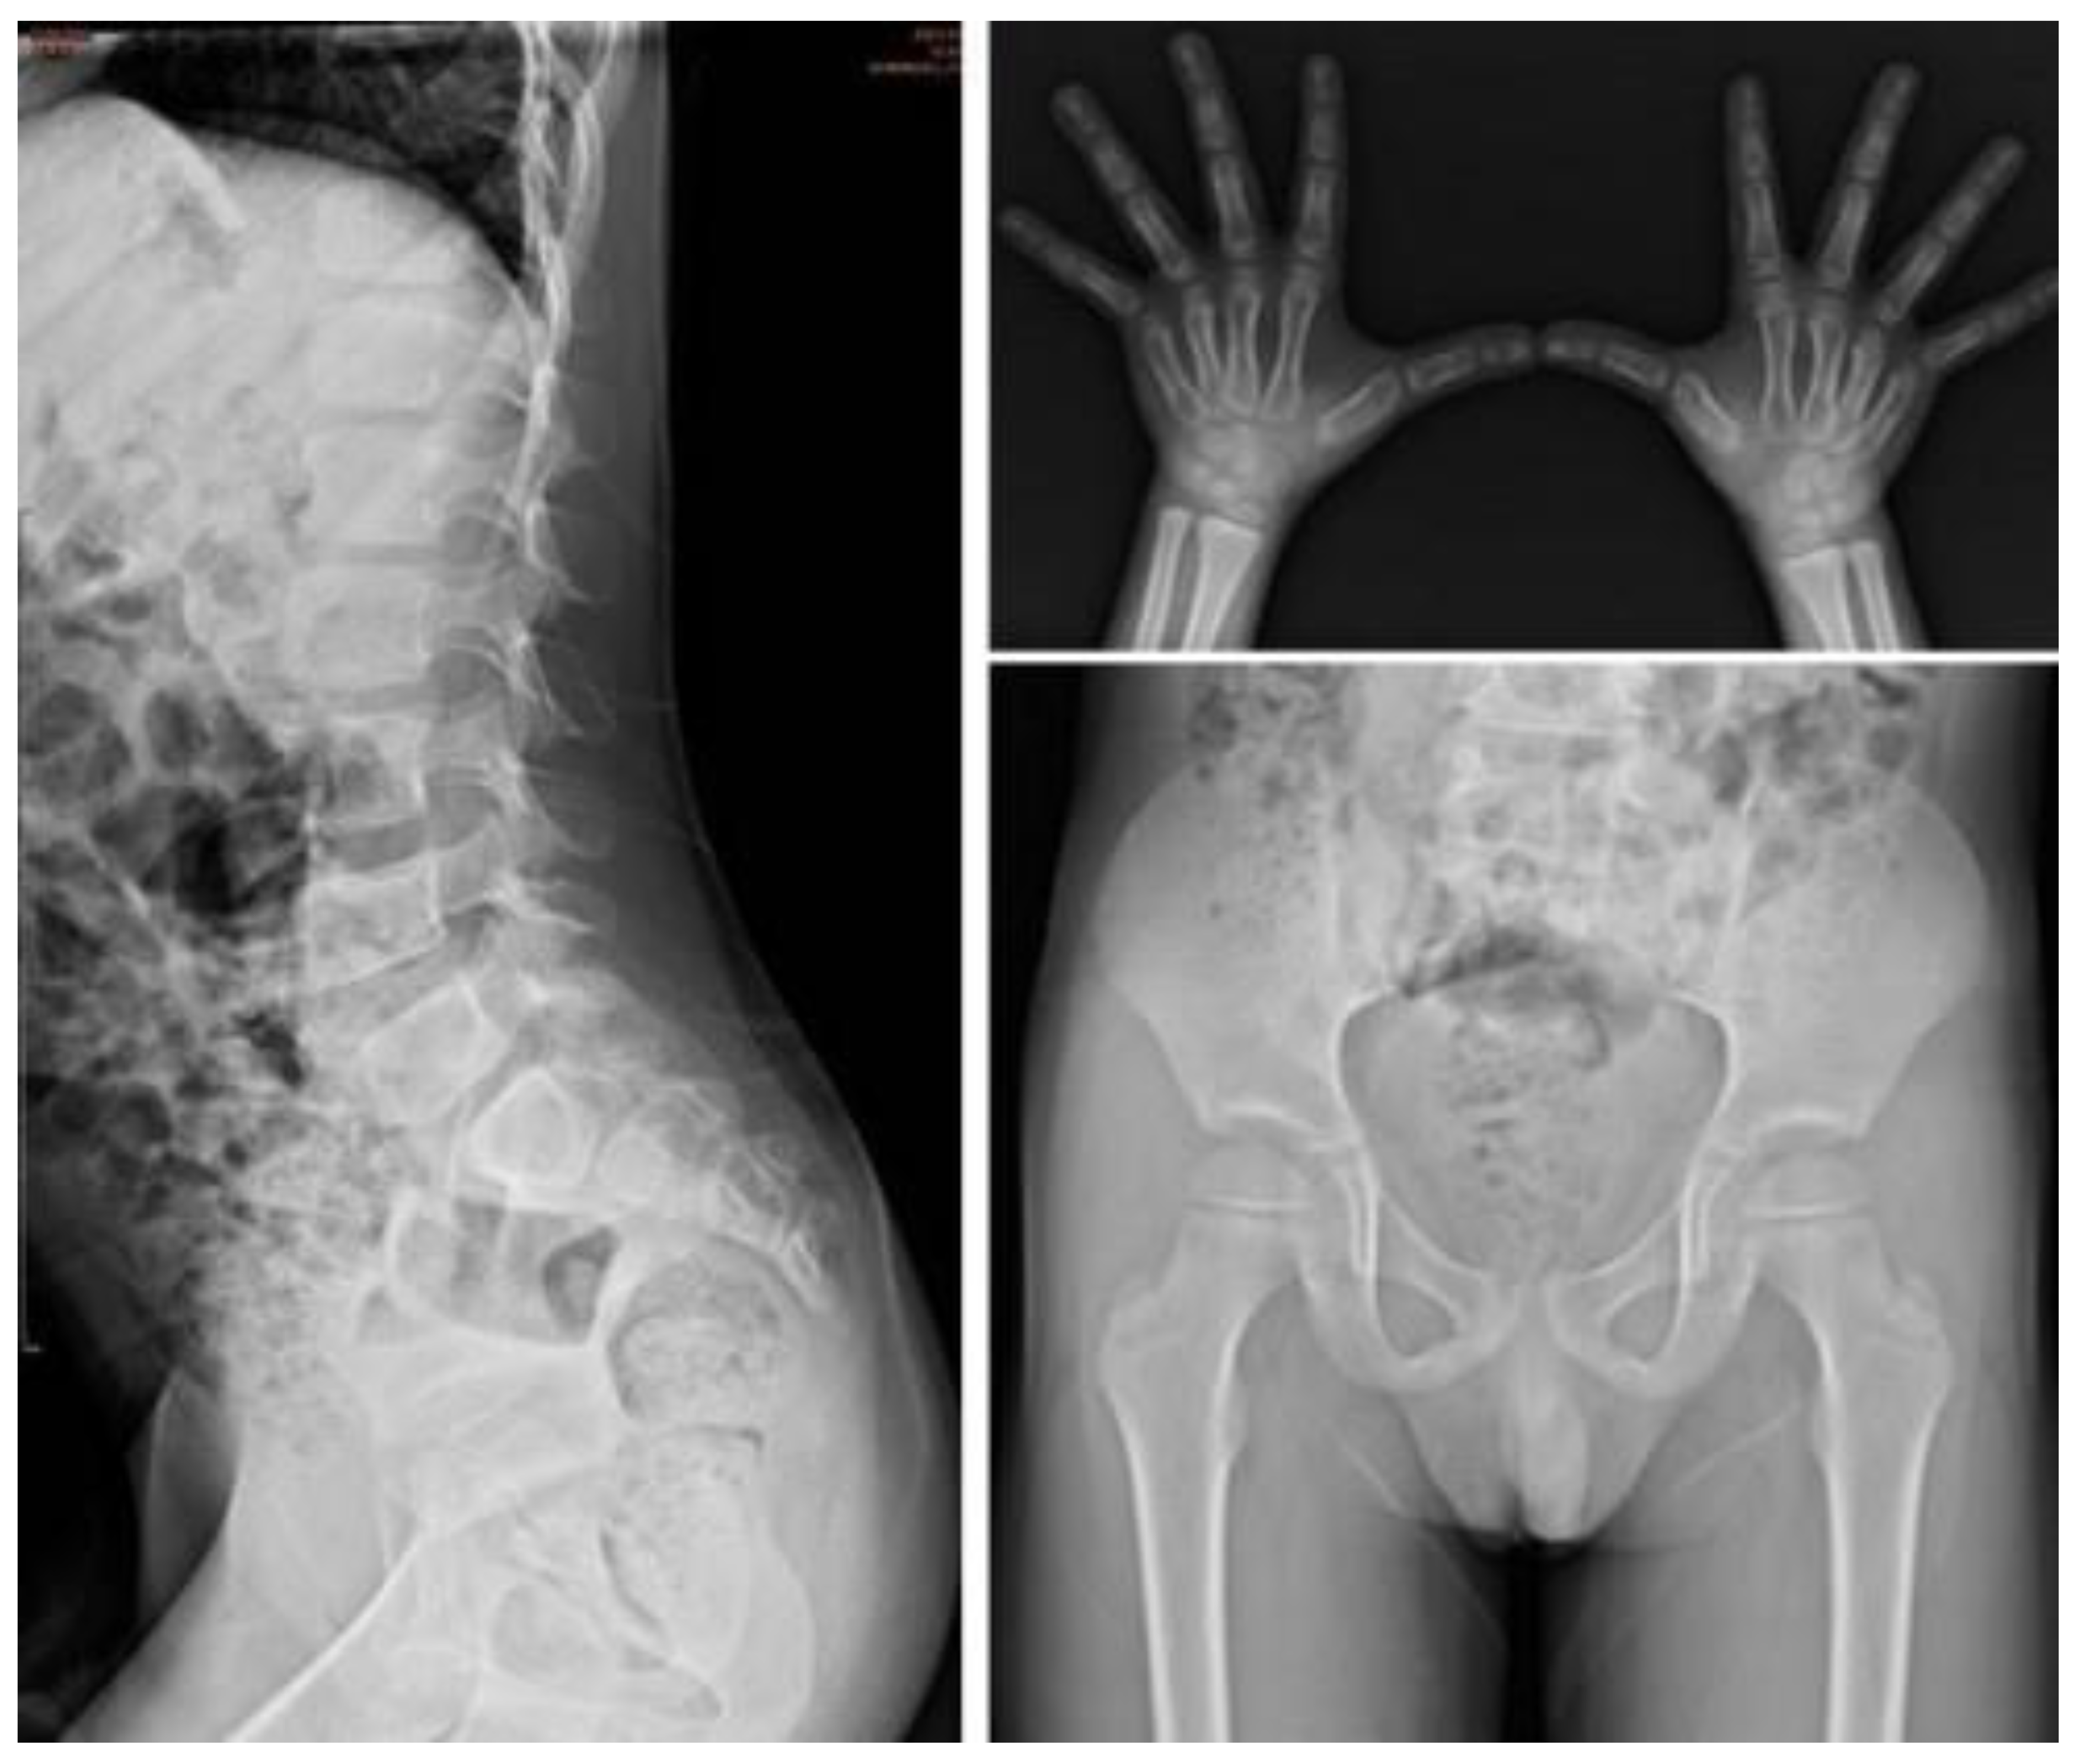

| I-5 | M | c.1400C > T, p.P467L | — | 0.5 | Baseline | 0.2 | 0.27 | 153.16 | 21.4 | 30.01 | 0.11 | Proximal tapering of metacarpal bone with bullet-shaped phalanges. | Normal | Normal | Normal | Normal |

| Follow-up | 3.5 | 7.51 | 18.01 | 0.42 | 3.28 | 2.39 | Suspicious of mild proximal tapering of metacarpal bone with bullet-shaped phalanges. | Multiplex dysostosis of the spine. L-spine vertebral bodies are round. The anterior beaking more at several vertebral bodies of L-spine. | Round iliac wings, inferior tapering of the ilea with not-well developed acetabulum. | Normal | Normal | |||||